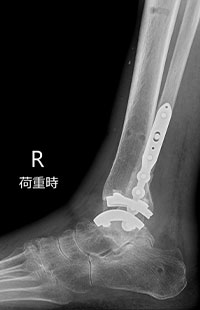

足くびの人工関節に加えて、足くびの中心にある「距骨(きょこつ)」という骨をセラミック製の「人工距骨」に置き換えます。セラミック製の人工距骨は強度が高く、生体とのなじみも良いです。

人工距骨の設計は、患者さんそれぞれのCT画像をもとに設計・製造された完全オーダーメイドです。完成までに2ヵ月程度かかります。

術前

術後